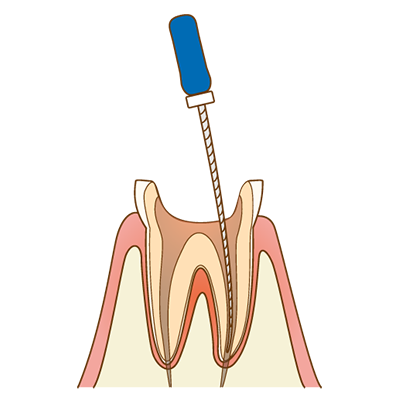

虫歯の除去・根管治療

神経まで達した虫歯の場合、根管治療を行います。マイクロスコープ下で虫歯を除去し、ラバーダムで隔離した清潔な環境で、歯の根の中を丁寧に洗浄・消毒します。根管は非常に細く複雑な形をしているため、拡大視野での治療が成功率を高めます。

根管の緊密な充填

根管内がきれいになったら、再び細菌が入らないように薬剤をすき間なく詰めます。この工程が不十分だと、数年後に痛みや腫れが出る原因となります。